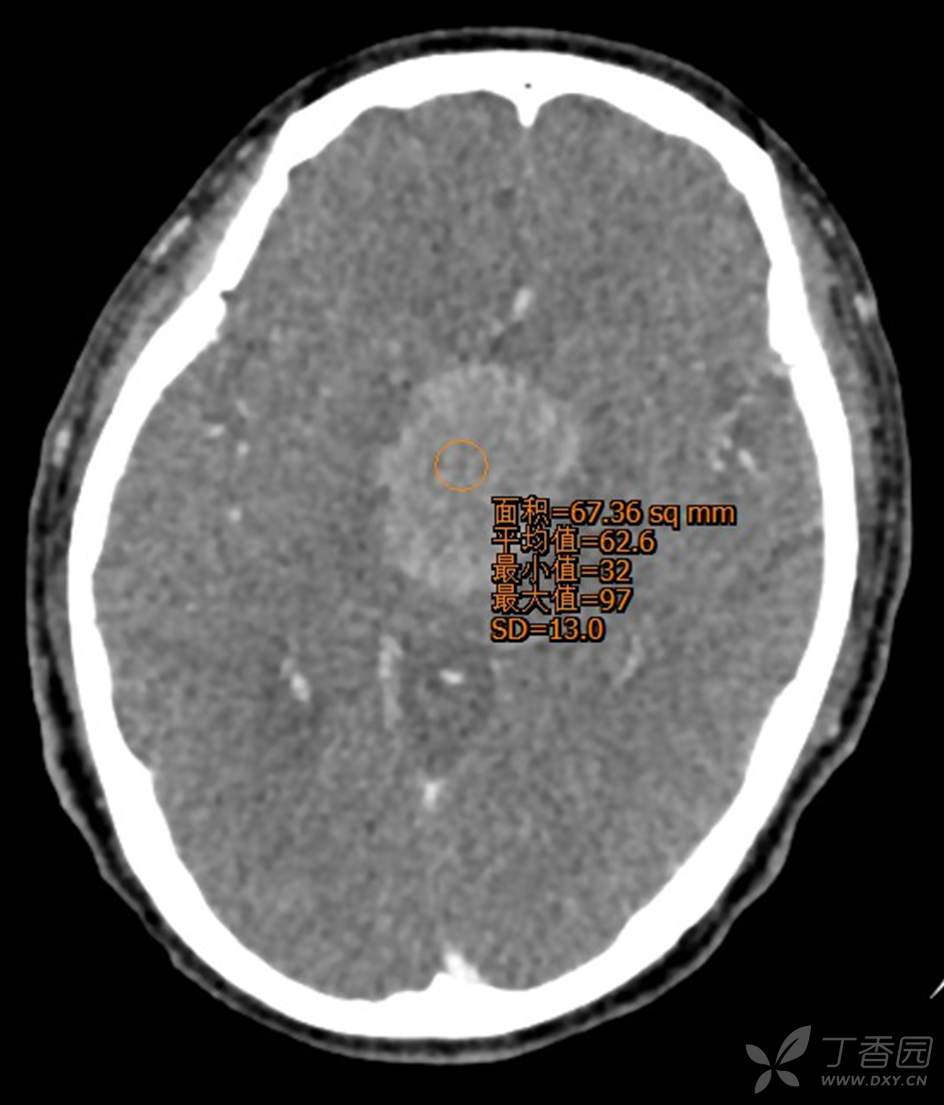

男,44岁,记忆力下降、乏力5月余,多尿3月余,CTMR全,疑难病例,能正确诊断吗?

图像不多,能诊断正确吗?有特征性吗?